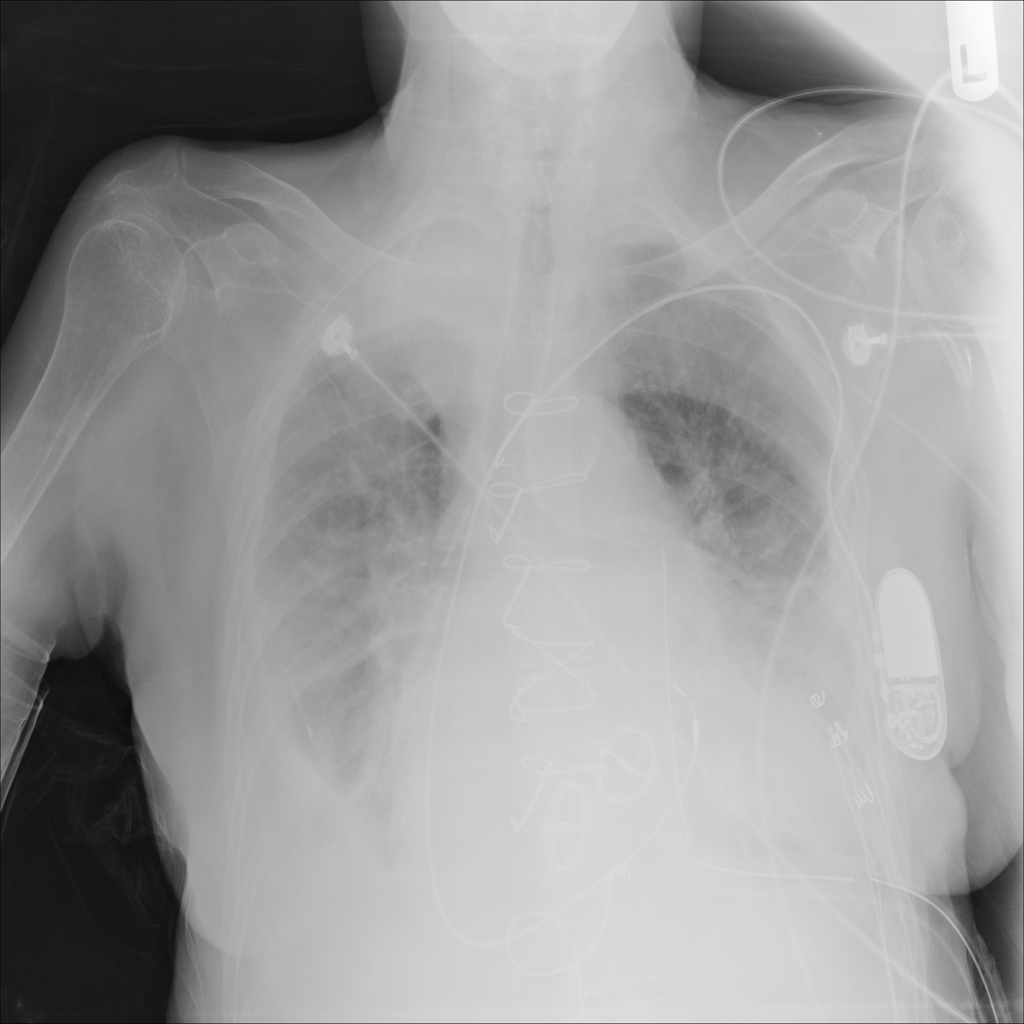

PAT-40F9 · IMG-004Effusion

PAT-40F9 · IMG-004

PA